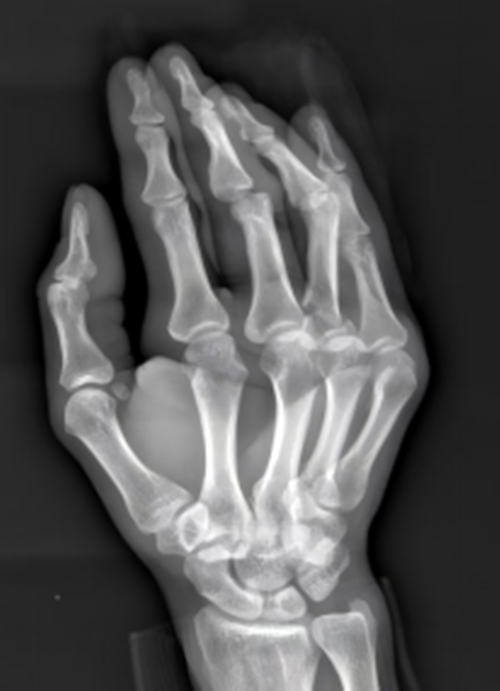

术前影像

以往,指骨骨折多采用克氏针或钢板内固定。然而,这两类方法各有不足:克氏针容易刺激周围软组织,可能影响屈伸肌腱的正常滑动;钢板固定则需要较大的手术切口,术后疤痕明显,且极易引发肌腱粘连。不少患者术后出现手指功能恢复迟缓、关节僵硬等问题,生活质量大打折扣,部分人甚至无法重返原有工作岗位。

52岁的林先生因外伤导致手指裂伤、指间关节脱位合并指骨骨折,一度担心术后会留下后遗症。接受微创置钉手术后,第二天他便在医生指导下开始进行轻度屈伸练习,一周后手指活动度已恢复大半。“不怎么痛,现在手指就可以活动了!”林先生的感慨道出了众多患者的心声。创伤骨科此项技术的成功应用,为手部功能的高质量恢复提供了新的保障。